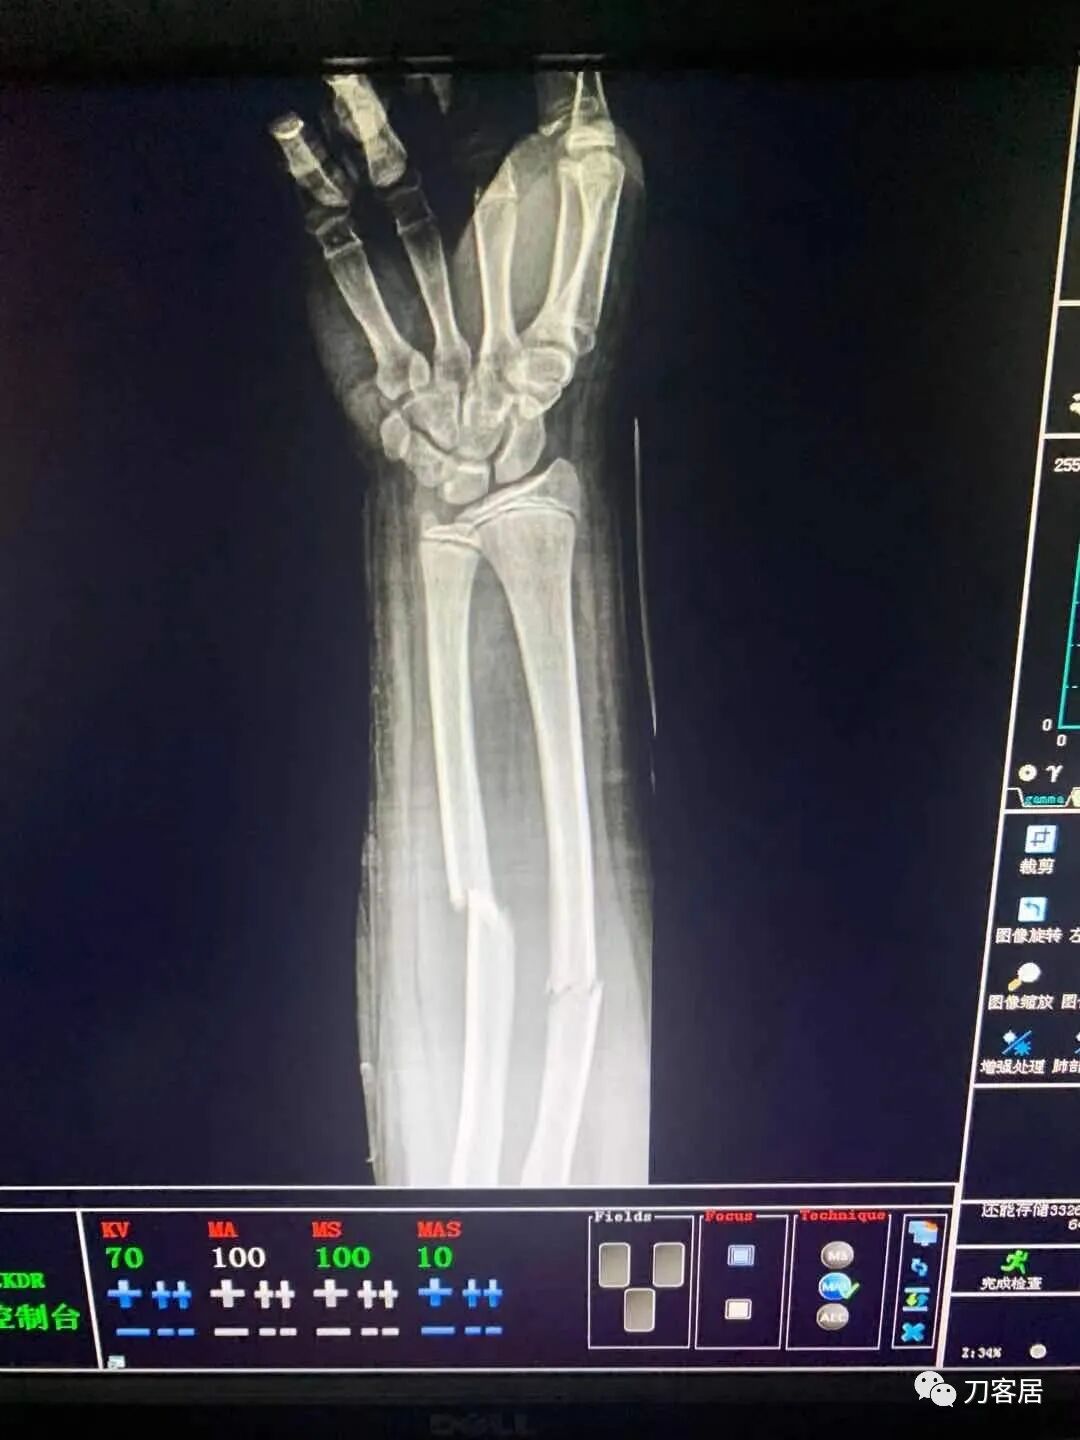

下面是这个6岁孩子,尺桡骨远端双骨折的术前及术后片子和外观照片。

2.  这个骨折处理起来也很简单,单纯的打石膏托或者中医的小夹板,或者正规的包括腕关节和肘关节的管型石膏外固定4周即可治愈该骨折。实在不行,如果这个孩子比较听话,不太调皮的话,用一本书,一个三角巾悬吊固定4周,都可以治愈该骨折。但是给这个患者用外固定架做了手术,而且桡骨远端的几颗克氏针距离骨折线太近,其中一枚克氏针进入到骨折间隙内。从这个术中图片来看,术者的外固定手术技术也有待于进一步的提高。毕竟术者应该还很年轻。从X线片来看,前臂及手的尺侧有不透光影,应该还使用了外固定石膏绷带托,而且我猜测应该是高分子的石膏绷带托,这个是纯属猜测,不一定是对的,不过如何解释前臂尺侧的不透光影呢?如果真是用了石膏绷带外固定的话,那为啥要做手术呢?外固定架术后就不该再用石膏绷带托辅助了。